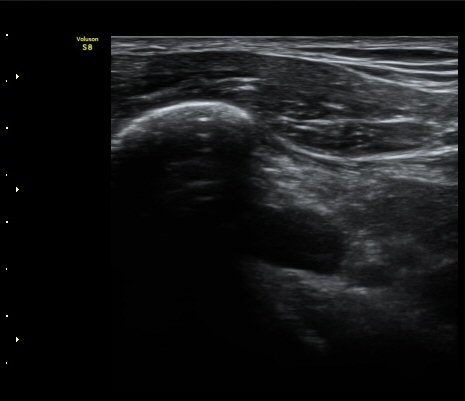

À̵ιڱ٠Á¾´Ü¸é°Ë»ç»ó ƯÀÌ ¼Ò°ßÀ» º¸ÀÌÁö ¾ÊÀ¸³ª(±×¸² 1)  ŽÃËÀÚ¸¦ ¾Æ·¡·Î À̵¿ÇÏ´Ï

°ß°©ÇÏ±Ù°Ç ³»Ãø¿¡¼­ ¼ö¾×Àú·ù°¡ °üÂûµÈ´Ù(±×¸² 2).